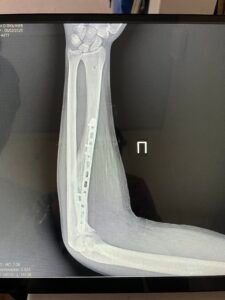

Наслідки важкого поранення обмежили функції руки, та час вимагає ставати в стрій і міцно тримати зброю. Та й правиця у коваля повинна бути міцною і вправною. Після мого повторного звернення Мирослав Ігорович, відгукнувся, спланував і успішно провів кісткову аутопластику дефекту 1 п’ястної кістки МОС пластиною та теноліз розгиначів 1 пальця.